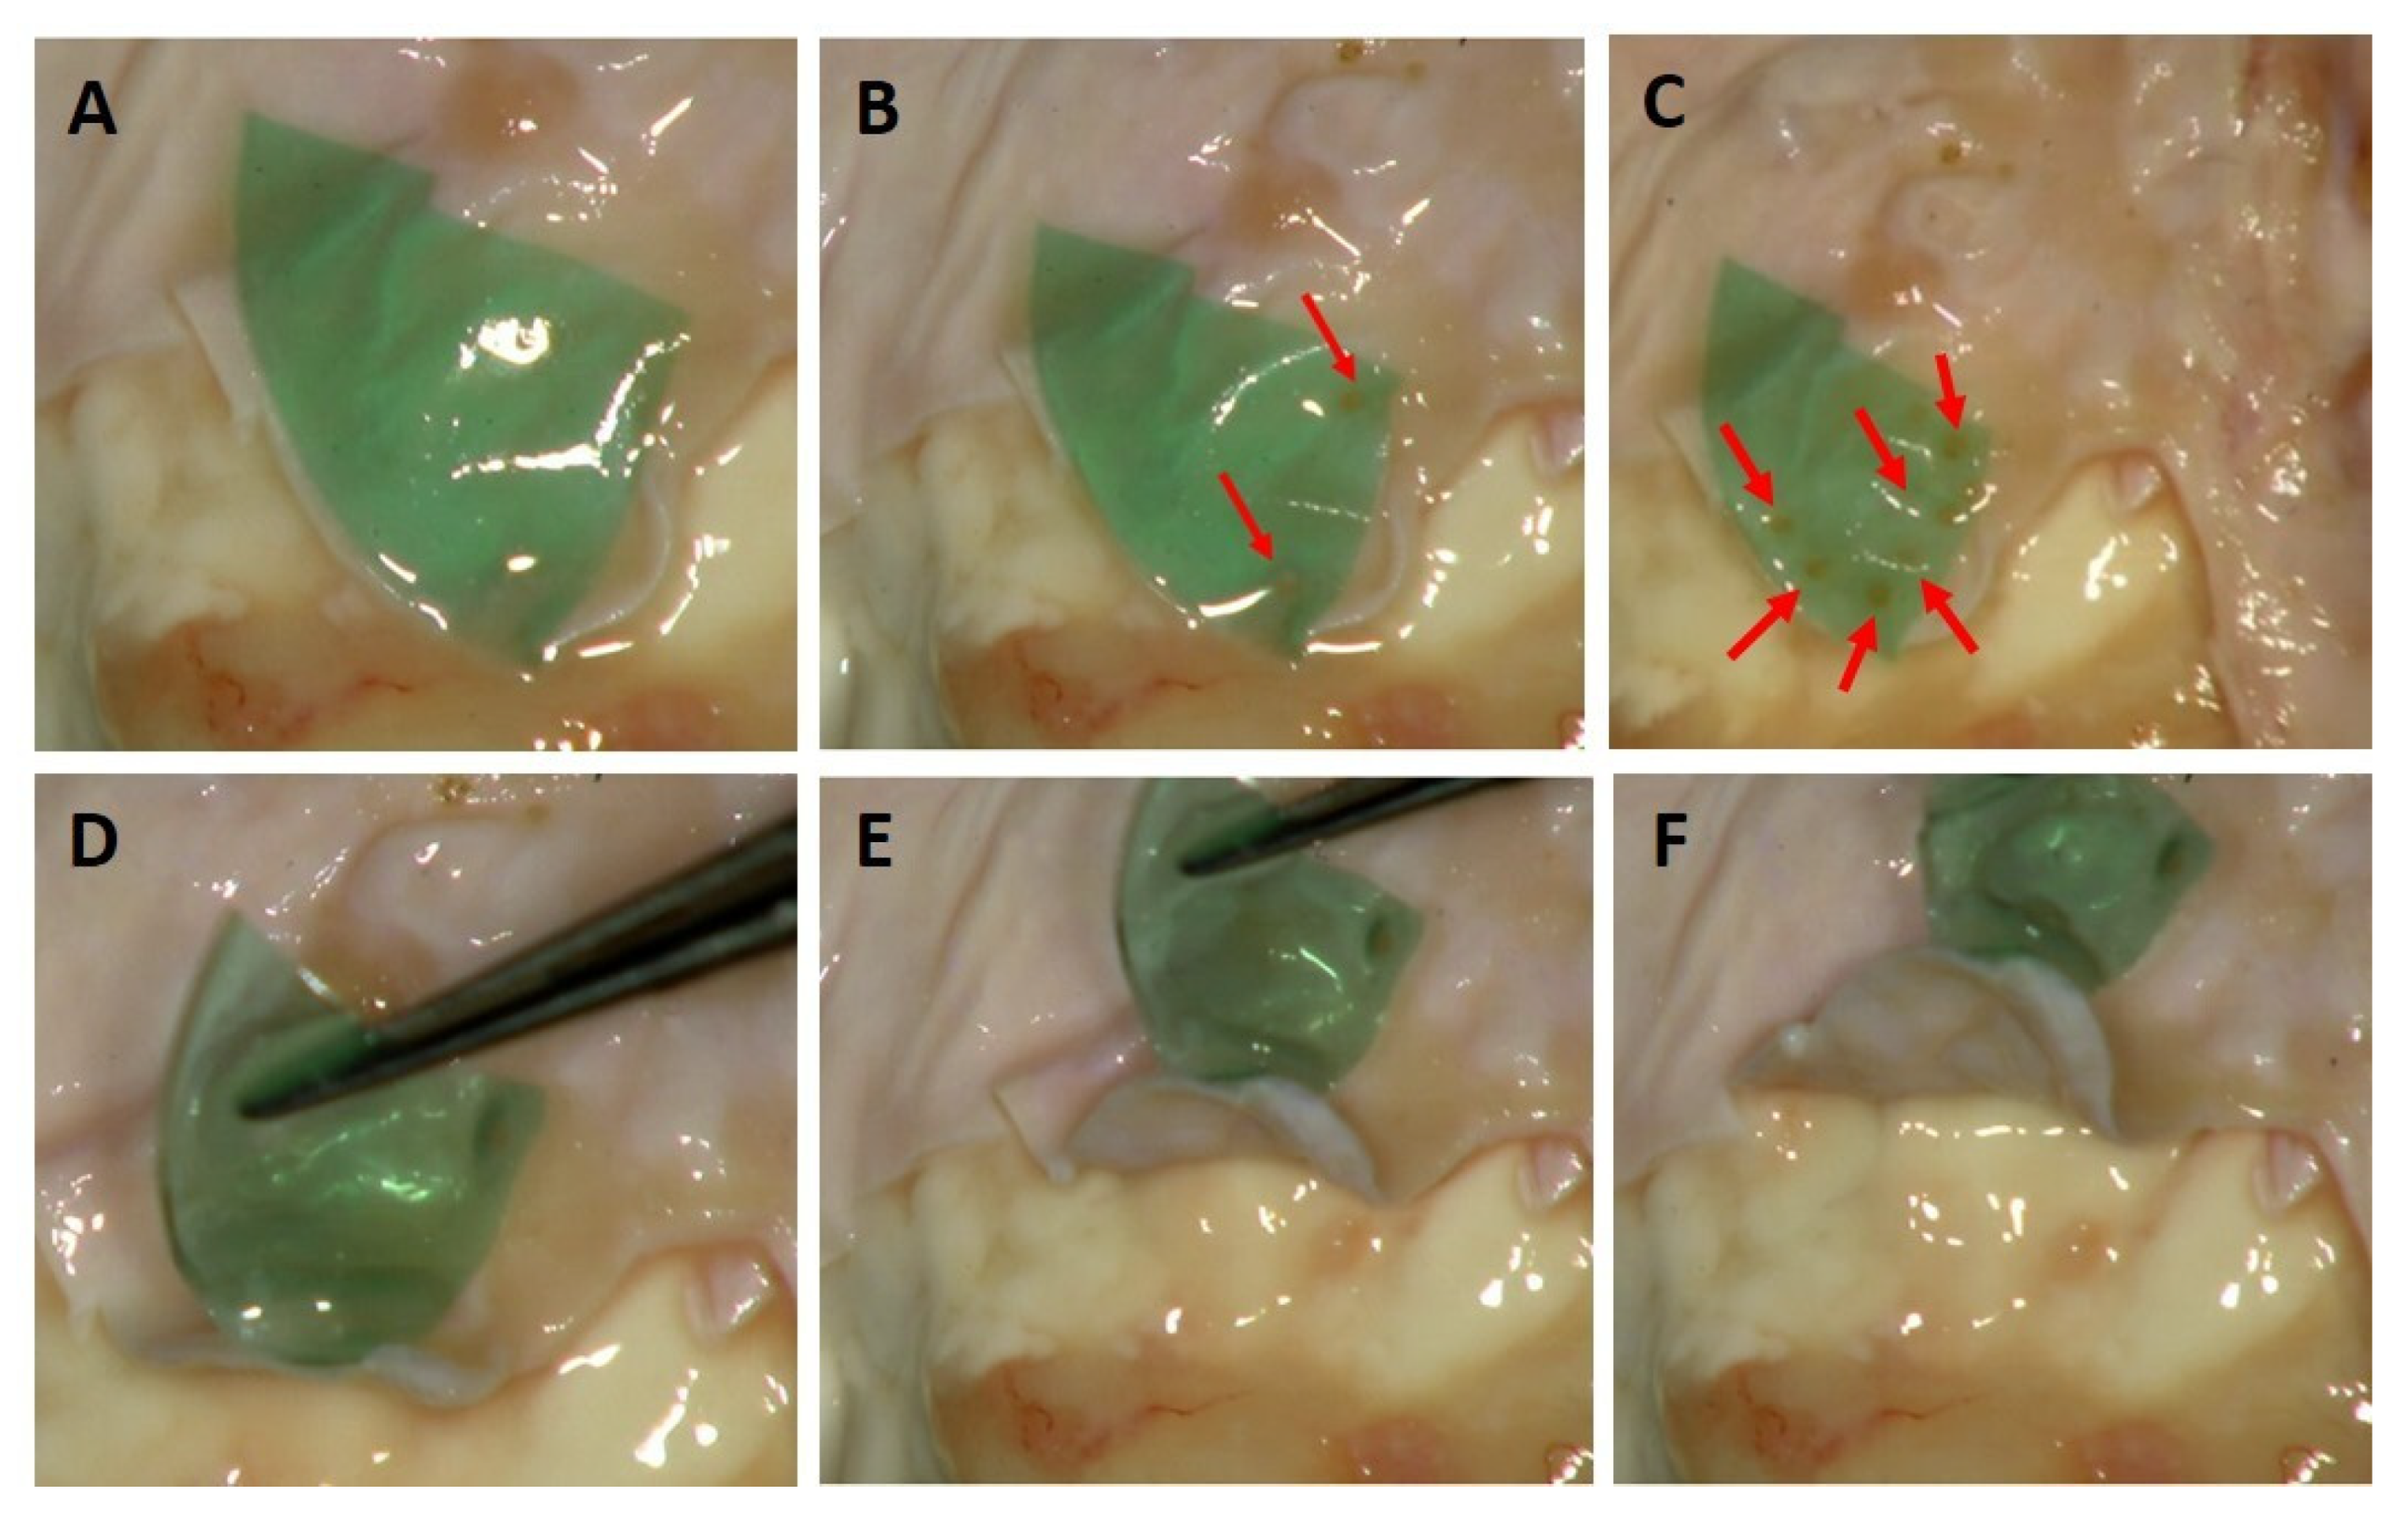

3.3. The Ex Vivo Tests in Dura Mater Laser Bonding